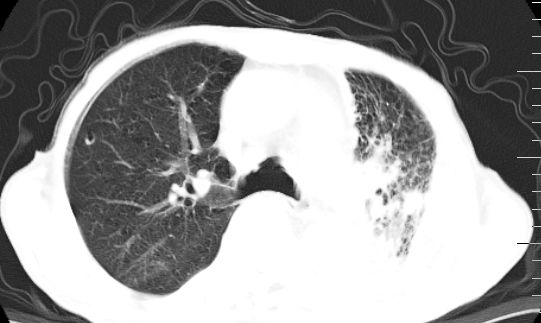

标题: CT10141:男、84岁,咳嗽、咯血1年。 [打印本页]

标题: CT10141:男、84岁,咳嗽、咯血1年。

支持左侧中央型肺癌伴下叶肺不张\\纵隔淋巴结转移.左侧包裹性胸腔积液\\心包积液.左侧少量胸腔积液..慢性支气管炎伴部分间质纤维化.

左肺中心性肺癌并肺不张,同侧 胸膜及心包转移,左肺癌性淋巴管炎

左肺中心性肺癌并左肺下叶肺不张,纵隔淋巴转移、同侧胸腔及心包积液(转移)。